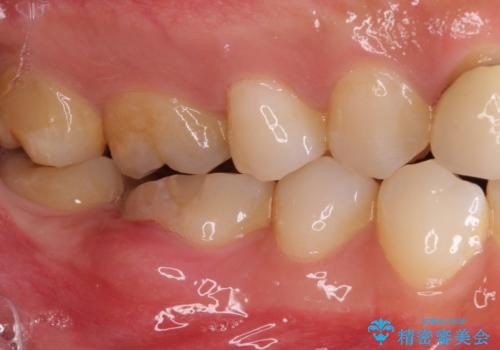

- 審美的ではない上の前歯とデコボコの下の前歯、歯茎が腫れている奥歯を気にして来院された患者様です。

根管治療の必要な歯がいくつかあるため、まずは根管治療を行い、その後インビザラインにて矯正治療を行うこととしました。

矯正治療後に前歯をセラミックブリッジに、奥の銀歯はセラミックインレーやPGAインレー(ゴールドインレー)にて補綴・修復治療を行うこととしました。

矯正治療により下顎前歯を整列させたため、上顎前歯のセラミックブリッジを補綴することで口元を少し下げることができました。